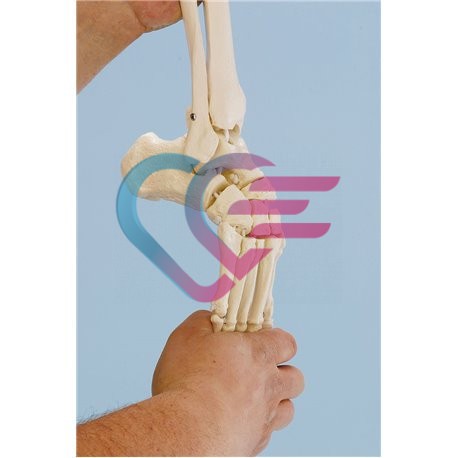

- Prvoklasni odljev kostura djeteta starosti 14 do 16 mjeseci.

- Prikazuje nesrasle epifize dugih kostiju i hrskavične rubove mnogih kostiju što je tipično za ovo doba razvoja.

- Sve fisure i otvori su pažljivo reproducirani.

- Udovi su ograničeno pokretljivi.

- Visina: 65 cm.

- Isporučuje se sa stalkom.

KOSTUR (SKELET) DJETETA STAROSTI 14 DO 16 MJESECI

ŠIFRA: KOSTU0010

- Prvoklasni odljev kostura djeteta starosti 14 do 16 mjeseci.

- Prikazuje nesrasle epifize dugih kostiju i hrskavične rubove mnogih kostiju što je tipično za ovo doba razvoja.

- Sve fisure i otvori su pažljivo reproducirani.

- Udovi su ograničeno pokretljivi.

- Visina: 65 cm.

- Isporučuje se sa stalkom.